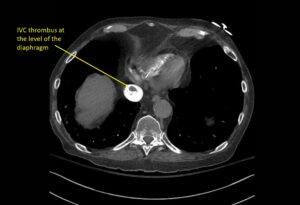

Wolff A, et al. Right atrial thrombosis. CT axial, IVC 2

Wolff A et al. Right atrial thrombosis. CT axial IVC 2